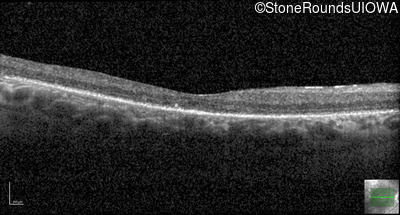

Optical Coherence Tomography - Right - 20/80 +1

Exemplar / OCT Stack

OCT Stack